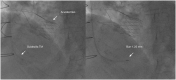

Case summary: We present the case of an 83-year-old woman with symptomatic severe AS, mildly decreased left ventricular ejection fraction and history of coronary artery bypass grafting with right internal mammary artery (RIMA) to the right coronary artery (RCA) and left internal mammary artery to the left anterior descending artery and further percutaneous coronary intervention (PCI) to the circumflex. First, we performed a transcatheter aortic valve implantation (TAVI) to treat the severe AS. Because of persistent symptoms despite good result, we then performed RA of the native RCA through the RIMA with a Guidezilla® guide extension catheter.

Discussion: A two-staged procedure of TAVI and PCI with RA of the RCA via RIMA was successfully performed. We decided to perform the PCI after the TAVI to allow a better haemodynamic tolerance of the complex coronary intervention. This procedure needs caution as the conduit is fragile and could be easily damaged during the RA. No data are available about feasibility and safety of RA through a native graft, but this could be a first step to consider it.